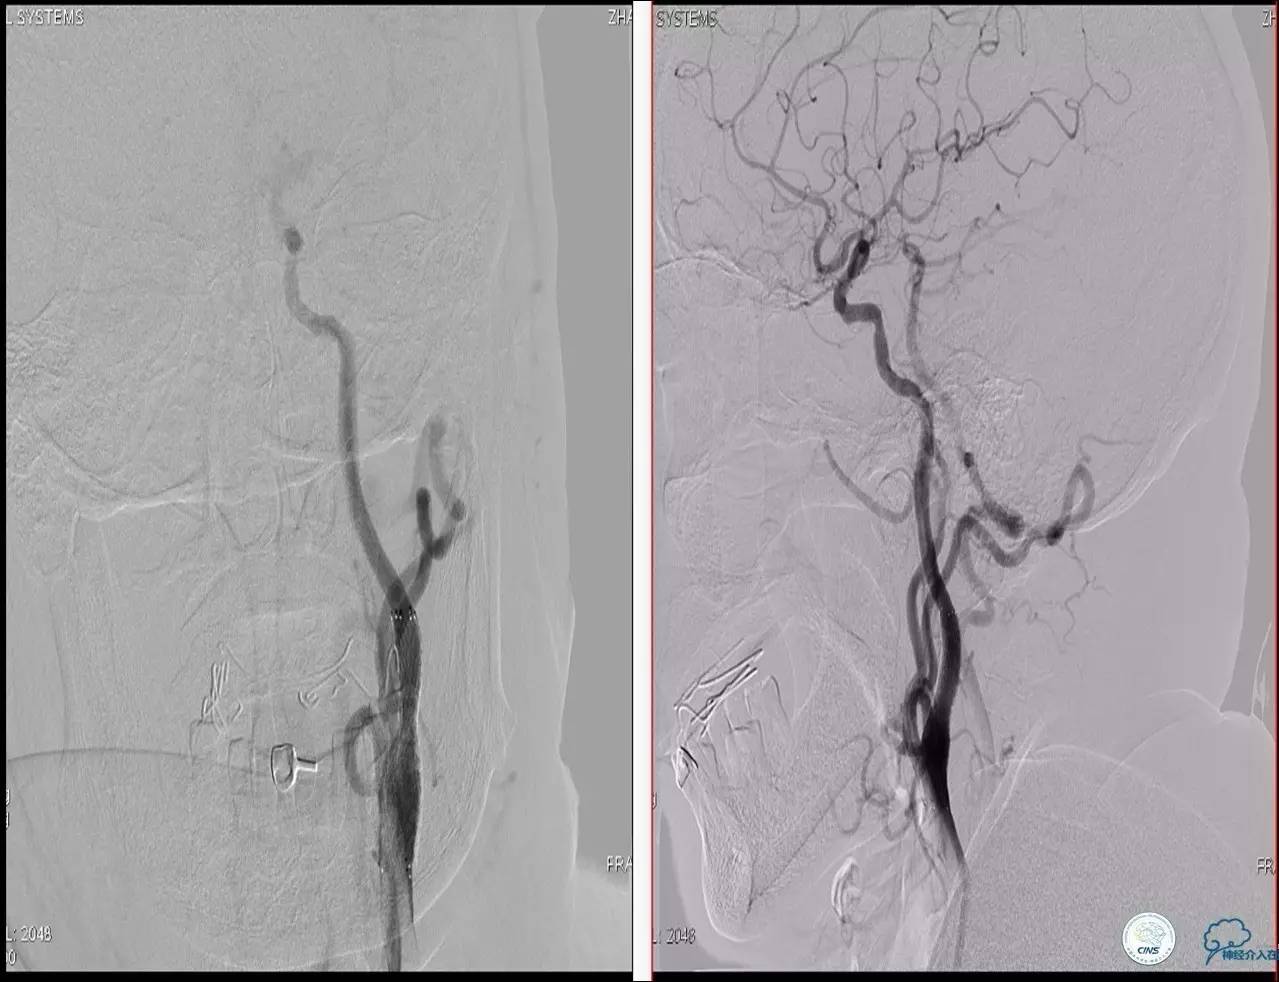

Case 2

》男,74岁。

》主诉:突发左侧肢体抽搐伴口角歪斜两月余,右侧肢体抽搐三天余。

》查体:左上肢肌力Ⅲ级,左下肢肌力Ⅳ级,右侧肢体肌力Ⅴ级。

》既往史:高血压病史。

》患者术后4小时出现右侧肢体无力,伴有癫痫样症状。

》考虑小栓子脱落,术中曾有后扩。